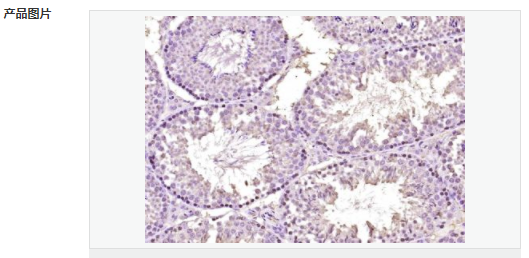

交叉反應:Human,Mouse(predicted:Rat,Dog,Pig,Cow,Rabbit) 推薦應用:IHC-P,IHC-F,ICC,IF,ELISA

產品應用ELISA=1:5000-10000 IHC-P=1:100-500 IHC-F=1:100-500 ICC=1:100-500 IF=1:100-500 (石蠟切片需做抗原修復)

Widely expressed in adult and fetal tissues. Present both in mesenchymal and epithelial cells in some adult tissues, including colon. Tends to be down-regulated in prostate adenocarcinomas and colorectal tumors due to promoter hypermethylation.